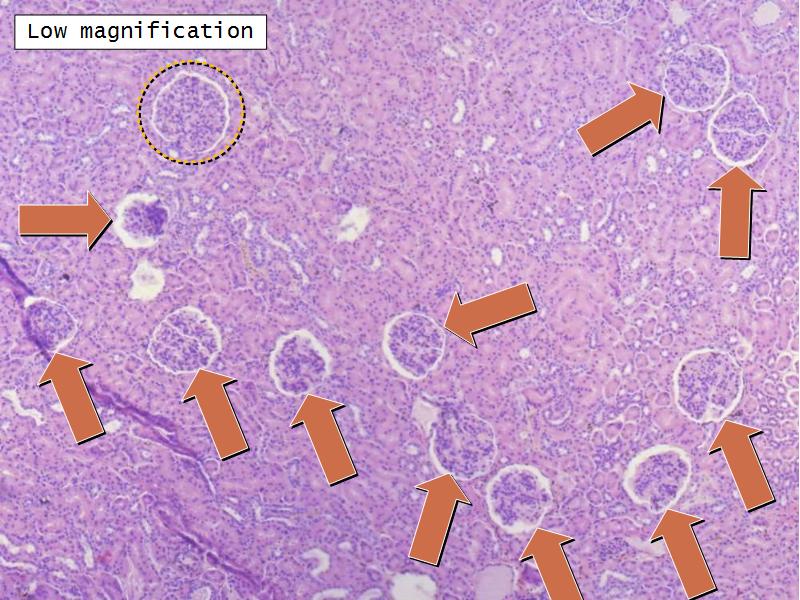

- The renal corpuscle

Nephron